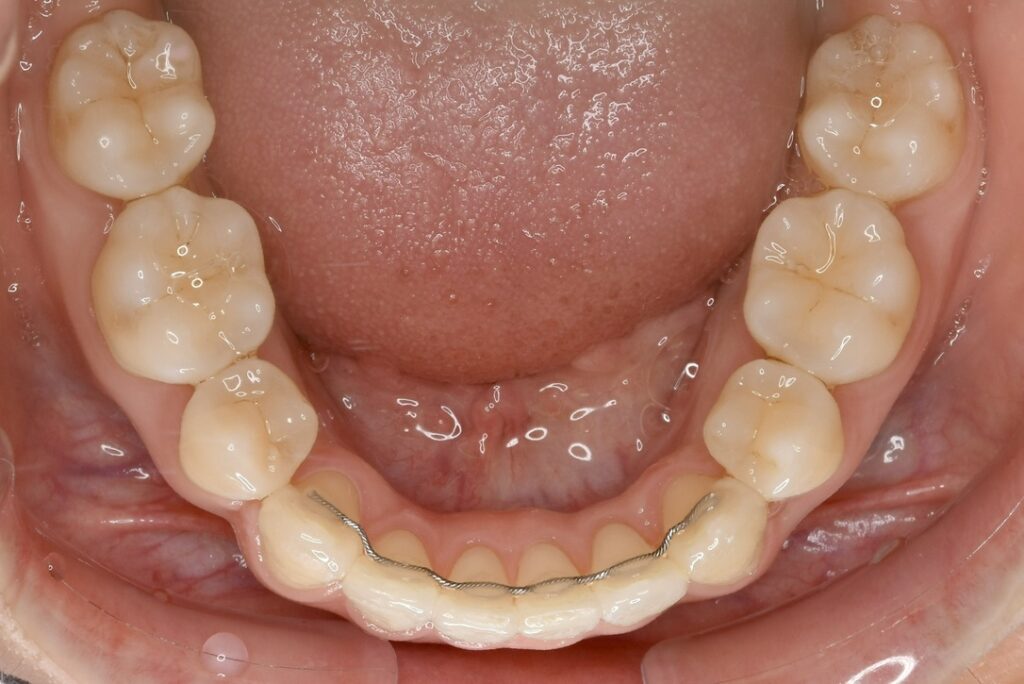

| 主訴 | 写真を見て歯並びが気になる。特に下の前歯はガタガタが強く治したい。 |

|---|---|

| 診断名・主な症状 | 叢生 |

| 年齢 | 19歳 |

| 治療内容 | 上下とも歯並びの幅を広げることでできたスペースを利用して、ガタガタを解消しました。 |

| 使用装置 | 表側矯正(ワイヤー) 矯正用ミニインプラント |

| 抜歯部位 | 抜歯なし |

| 治療期間 | 1年10ヶ月 |

| 通院回数 | 25回 |

| 費用 | 91万円程度(税別) 220 |

| リスク・副作用 | 痛み、歯肉退縮、歯根吸収、抜歯に伴う出血や腫れが生じることがあります。 |